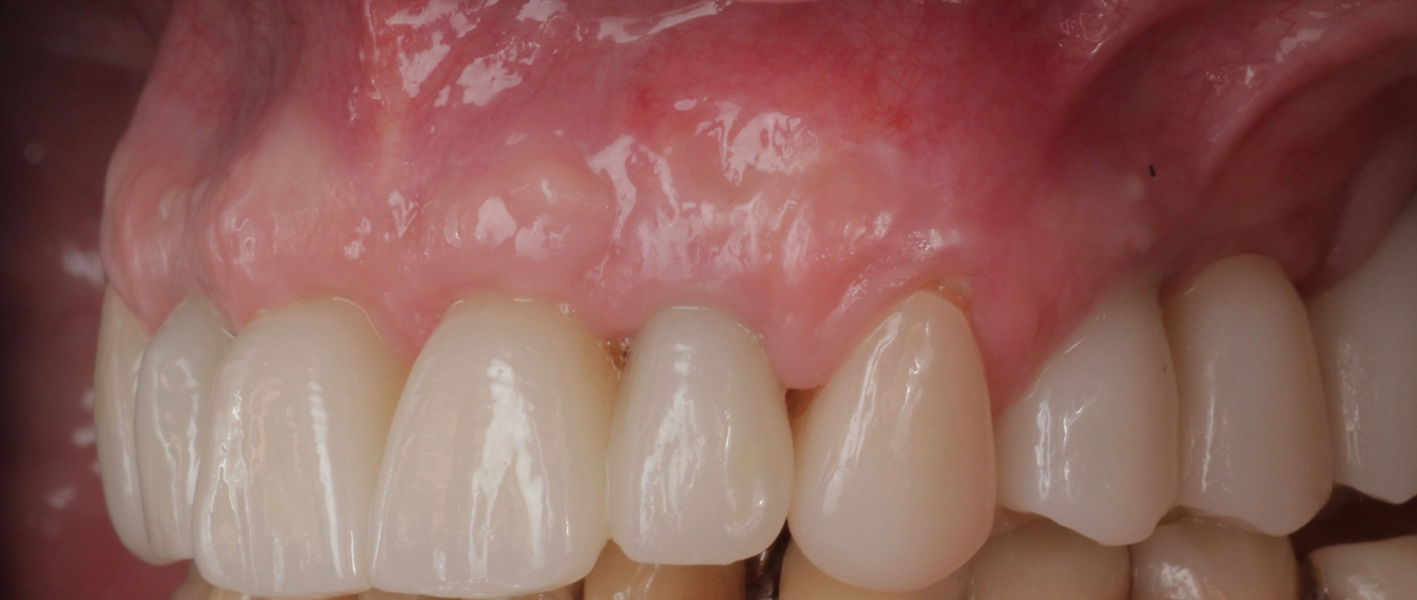

Definitive prosthetic treatment was performed after completion of implant healing with three CAD/CAM-fabricated monolithic zirconia bridges (DD cubeX2, Dental Direkt). The bridges were screwed on to BEGO titanium base abutments (Figs. 14–16). Good fit of the prosthetic superstructures was displayed in the radiograph after placement (Fig. 17). The two-year follow-up examination in July 2019 revealed excellent aesthetic and clinical soft-tissue conditions (Figs. 18–20). No radiographic bone loss had occurred at the implant sites (Fig. 21). Neither the submerged central incisors nor the distobuccal molar root displayed any signs of periapical inflammation, and the patient reported no complications. The patient’s oral hygiene had improved significantly during the follow-up period.

Fig. 14: Frontal aspect of the definitive prosthetic restorations, showing good aesthetic conditions with no signs of soft-tissue complications after insertion.

Fig. 15: Right lateral aspect of the restorations.